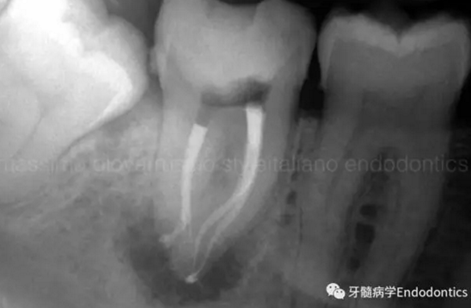

圖6.術(shù)后X線片顯示在根管機(jī)械預(yù)備后保留了原始的根管解剖形態(tài)結(jié)構(gòu)。冠方預(yù)敞和探查保證了對(duì)整個(gè)根管解剖形態(tài)結(jié)構(gòu)的保護(hù)。